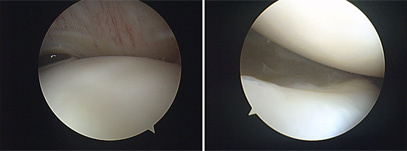

Segundo Stephen Snyder, os pontos articulares que devemos avaliar na artroscopia do ombro são:

- Tendão do bíceps e labrum superior;

- Ligamentos gleno-umeral superior, médio, tendão subescapular, labrum anterior, labrum inferior e superfície glenoide;

- Gleno-umeral anteroinferior e recesso axilar;

- Tendão supraespinhoso (articular), manguito posterior e “bare area”;

- Superfície articular umeral e labrum posterior.

Após a avaliação do espaço articular, reposicionamos o artroscópio para avaliar o espaço subacromial. Nesse local, podemos identificar patologias da bursa subacromial, do manguito rotador, do acrômio, do ligamento coracoacromial e da articulação acrômioclavicular.